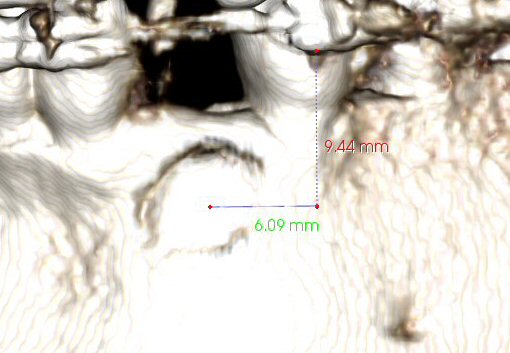

CBCT provides us with the information such that we can perform the surgical exposure of the impacted canine accurately and precisely. We need to know the location of the center of the surgical site and how much bone that must be removed without touching the crown of the tooth (see Figs. 16-18). The numbers shown are the exact measurements, but the surgical doctor can deviate from those a bit (~0.25 mm).

Fig. 17 CBCT, showing location of center of surgical site: ~ 9 mm down (from bottom of bracket on LL4), ~ 6 mm left (of viewer).

© Copyright 2007-2014, Vu Orthodontics. All rights reserved.

Fig. 18 CBCT, showing ~ 0.7 mm of cortical bone that must be removed, with ~ 0.6 mm space before touching the crown.